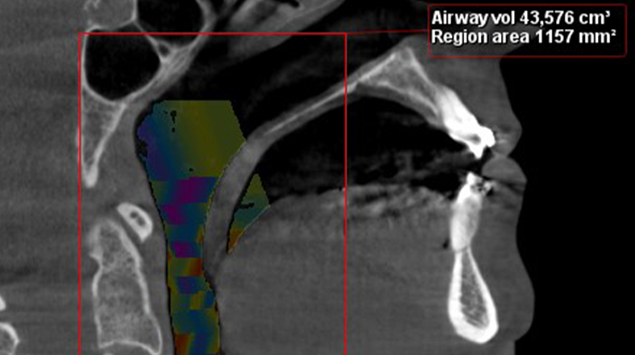

>   Zmiana w objętości dróg oddechowych po leczeniu ortodontyczno-chirurgicznym o ponad 70%